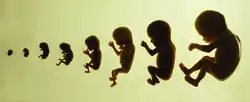

Viabilidade

Estágios em desenvolvimento pré-natal, mostrando viabilidade e ponto de 50% de chance de sobrevivência na parte inferior. Semanas e meses contados por gestação.